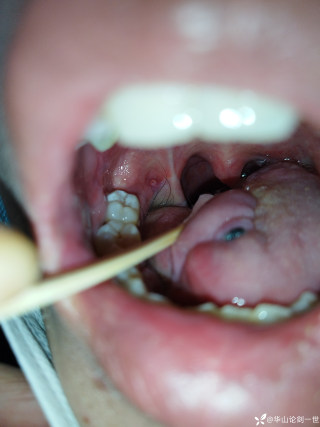

烧伤整形邹普功烧伤科医师

活动背景和目的:我从去年九月份陆续在丁香园写了几十帖有关腋臭微创手术的帖子,受到很多同行老师的关注及跟帖,其中有很多同行老师也在尝试用我的这种方法治疗狐臭,并且收到很好的效果。随着站内外科同行对狐臭微创手术的关注度日渐增高,近期受丁香园邀请,特举办一次关于狐臭微创手术的跟学练活动。这也是本人根据临床工作中的一些手术案例总结的经验,分享给大家一起交流学习。让我们一起做好除臭这件事!各位站友可点击下面狐臭专场链接交流学习(包含本人视频操作教学详解、常见问题讨论和各位站友同行的手术佳作):https://3g.dxy.cn/newh5/view/nodeActivityTopic/270第一期我给大